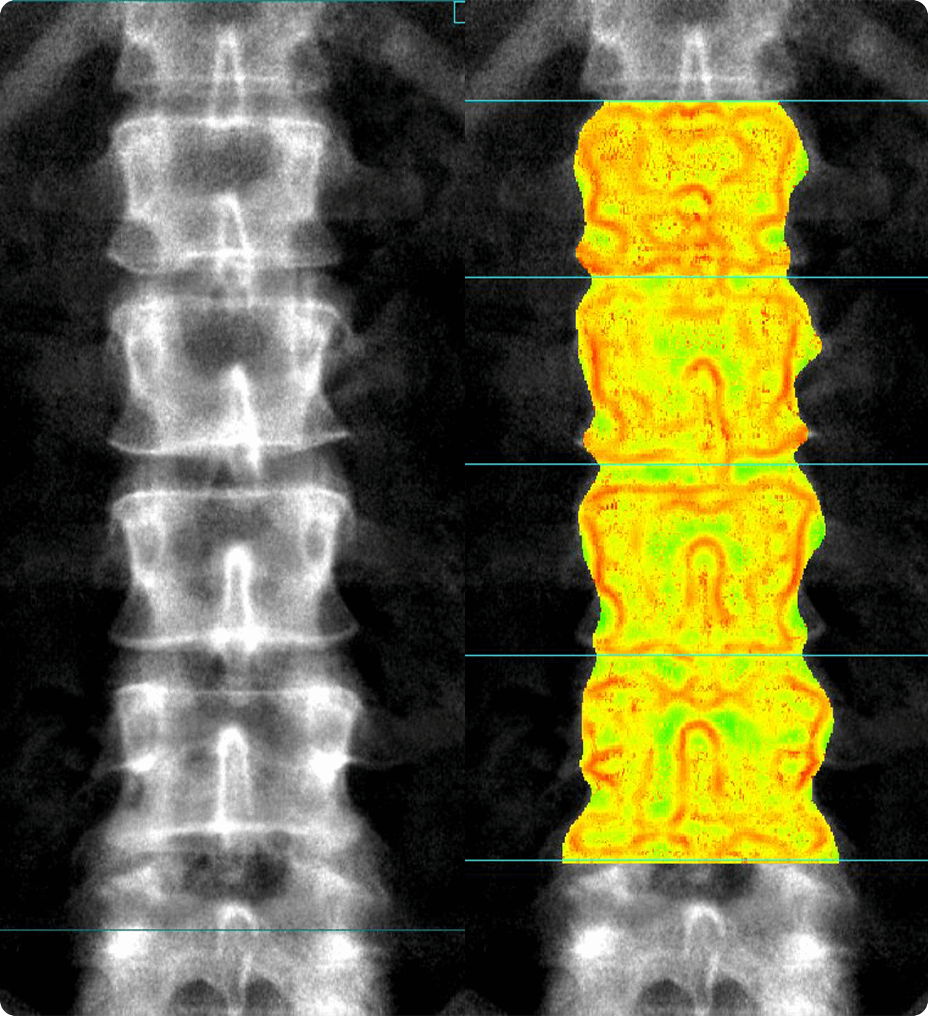

Perfusion maps and tissue classification

• Fully integrated with CT Perfusion 4D for visualization of perfusion functional maps³

• Deep Learning brain ventricle segmentation to prevent ventricular matter inclusion in quantitative results and improve visual inspection of the maps

• Automated computation of the functional maps

• Tissue Classification map segmented from absolute or relative values, customizable thresholds and user selectable input maps

• Mismatch volume and ratio calculated from the Modified Perfusion region and the Low Perfusion region